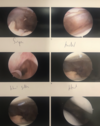

Identified and unstable chondral flap the medial femoral condyle that was amenable to chondroplasty.

Using both a straight biter and a rotary shaver I debrided to a stable rim.

I then completed the diagnostic arthroscopy without any additional pathology identified. Duration of surgery was 25 minutes with 10cc estimated blood loss.